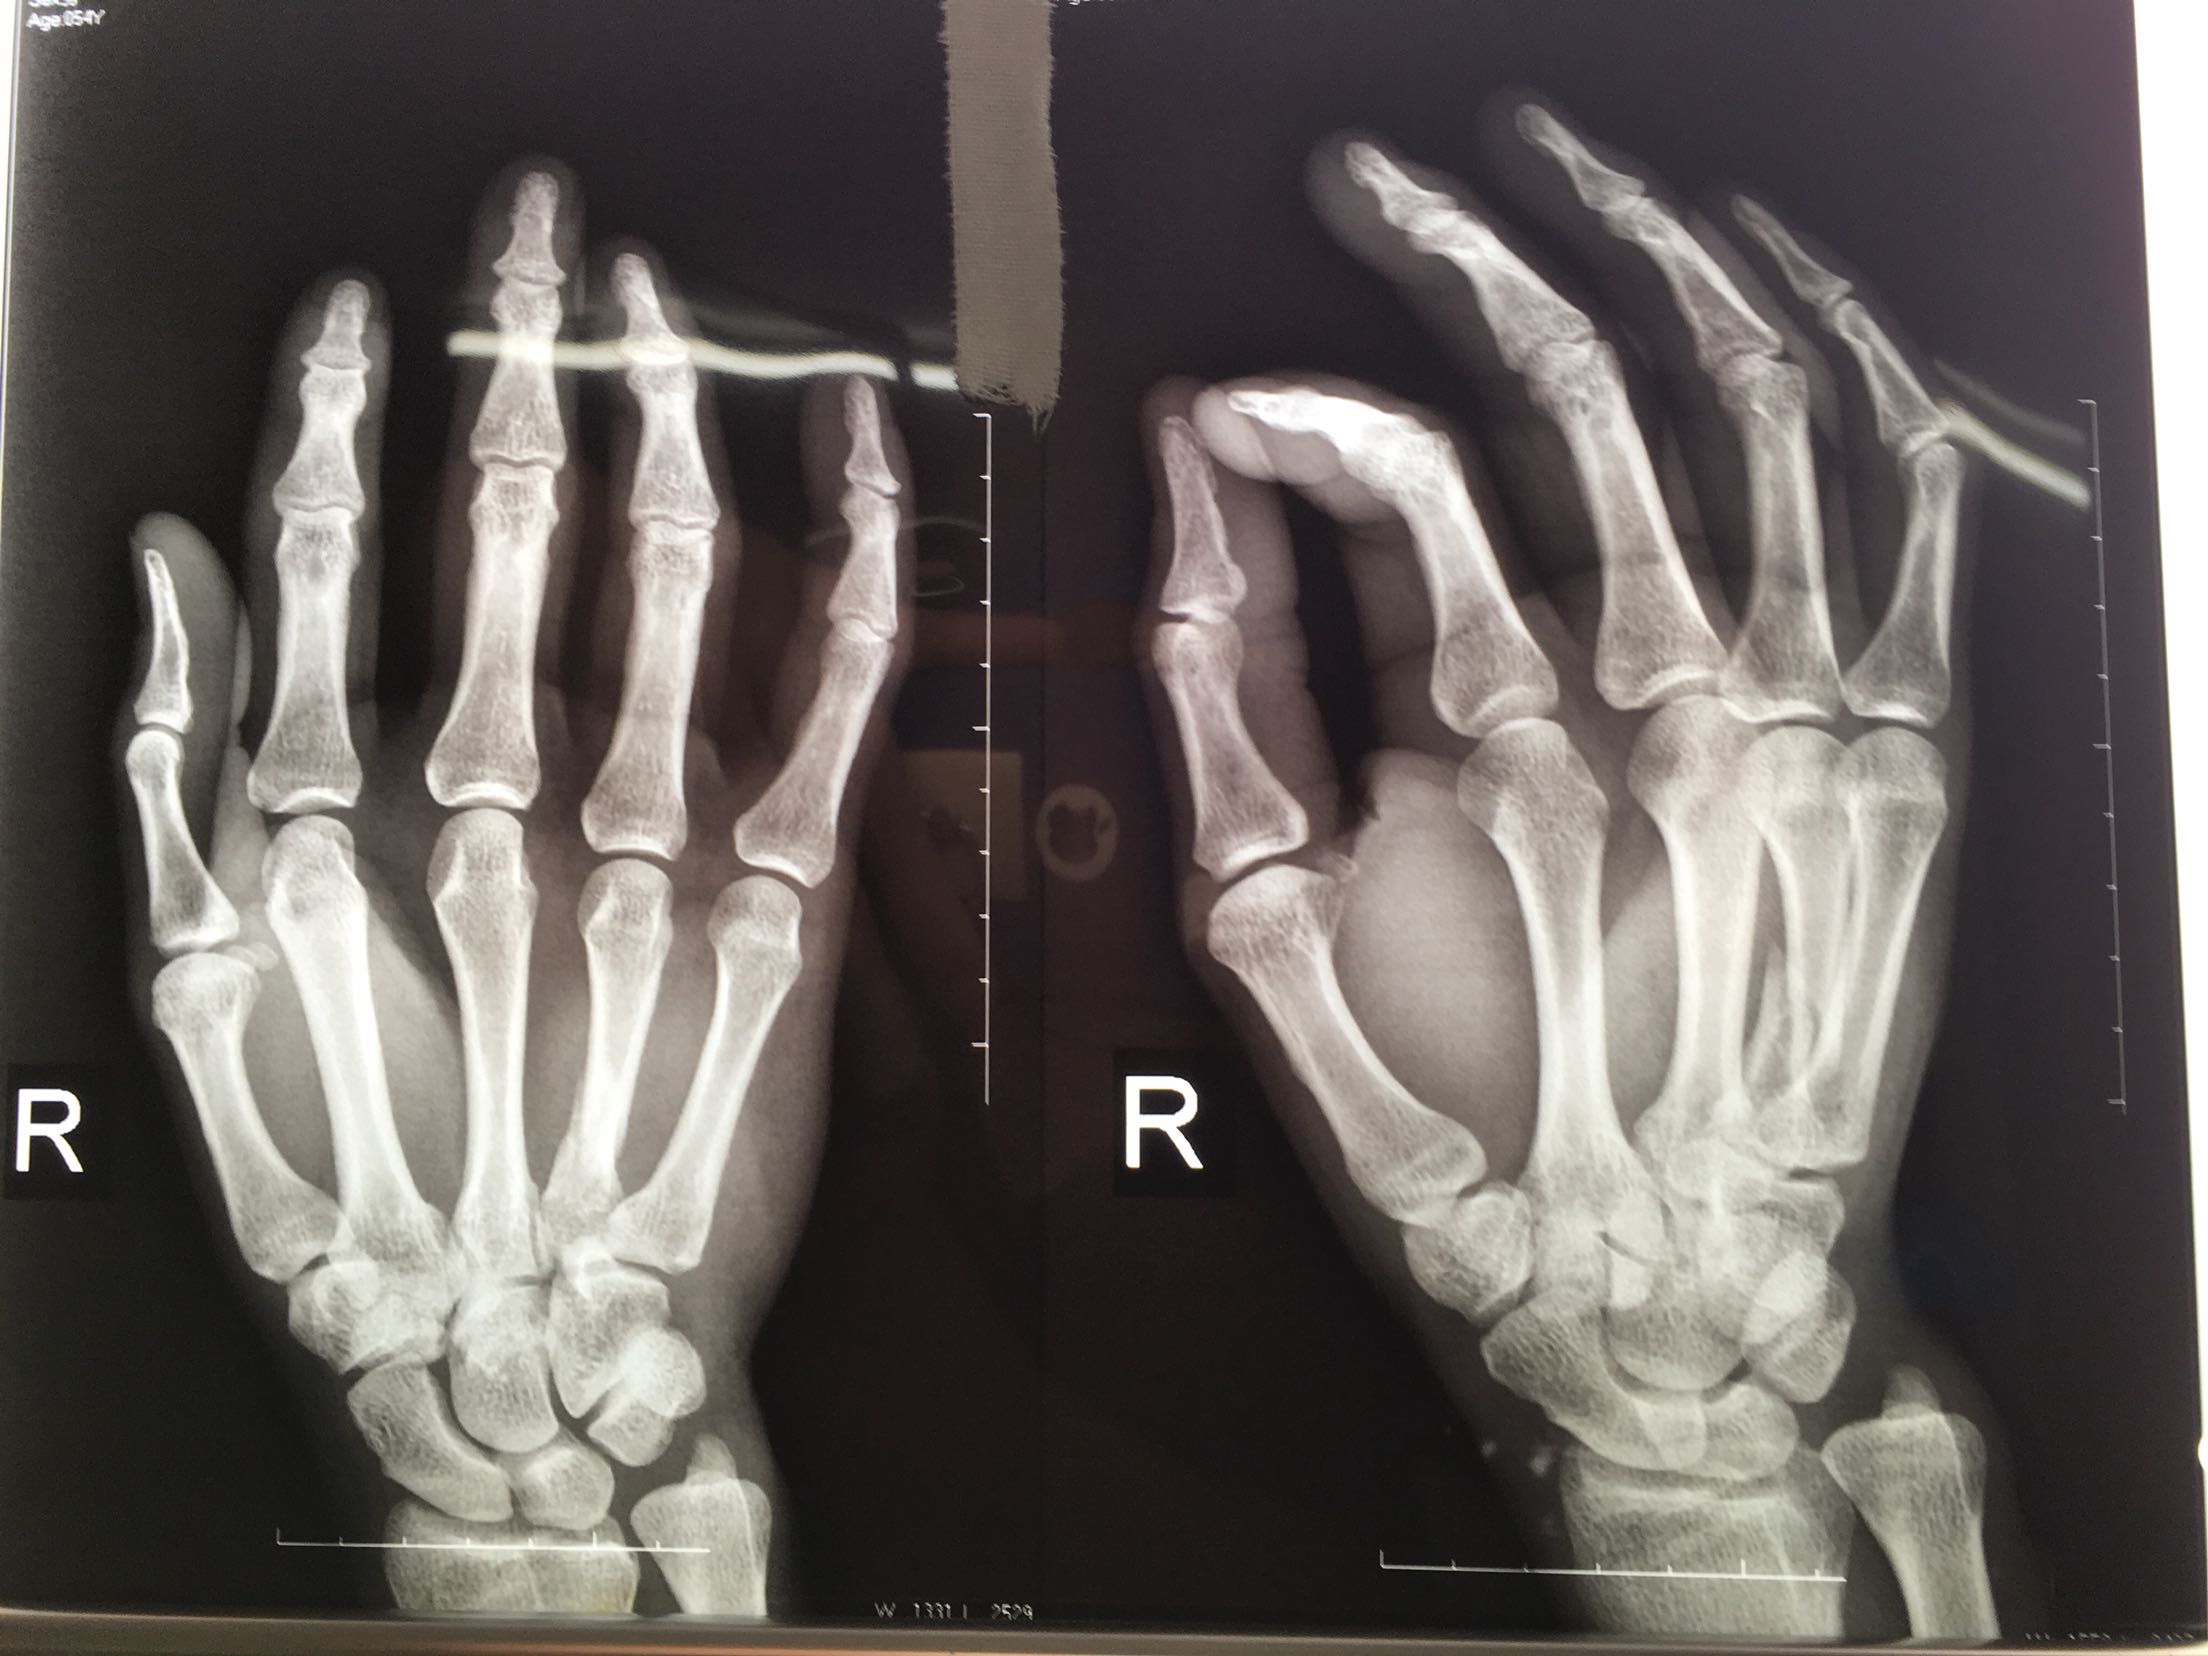

患者,男,52岁,摔伤后右手肿痛,活动受限4小时入院。

右手掌肿胀明显,皮色皮温正常,局部压痛,纵叩痛阳性,可及骨擦感,第四掌指关节活动受限,末梢血运感觉正常。

完善检查,在臂丛麻醉下行切复内固定术,术后抗炎,消肿止痛处理。